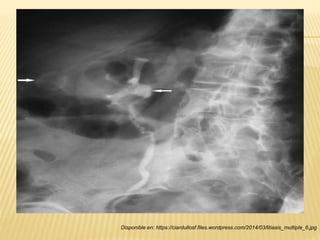

Disponible en: https://ciardullosf.files.wordpress.com/2014/03/litiasis_multiple_6.jpg

“RADIOGRAFÍA Y ECOGRAFÍA DIRIGIDA”

 80-90% de los cálculos

son visibles.

 Imágenes radiopacas.

Se valora:

- Forma (circulares,

ovoides, amorfos).

- Tamaño (1-8 cm de

diámetro).

- Número